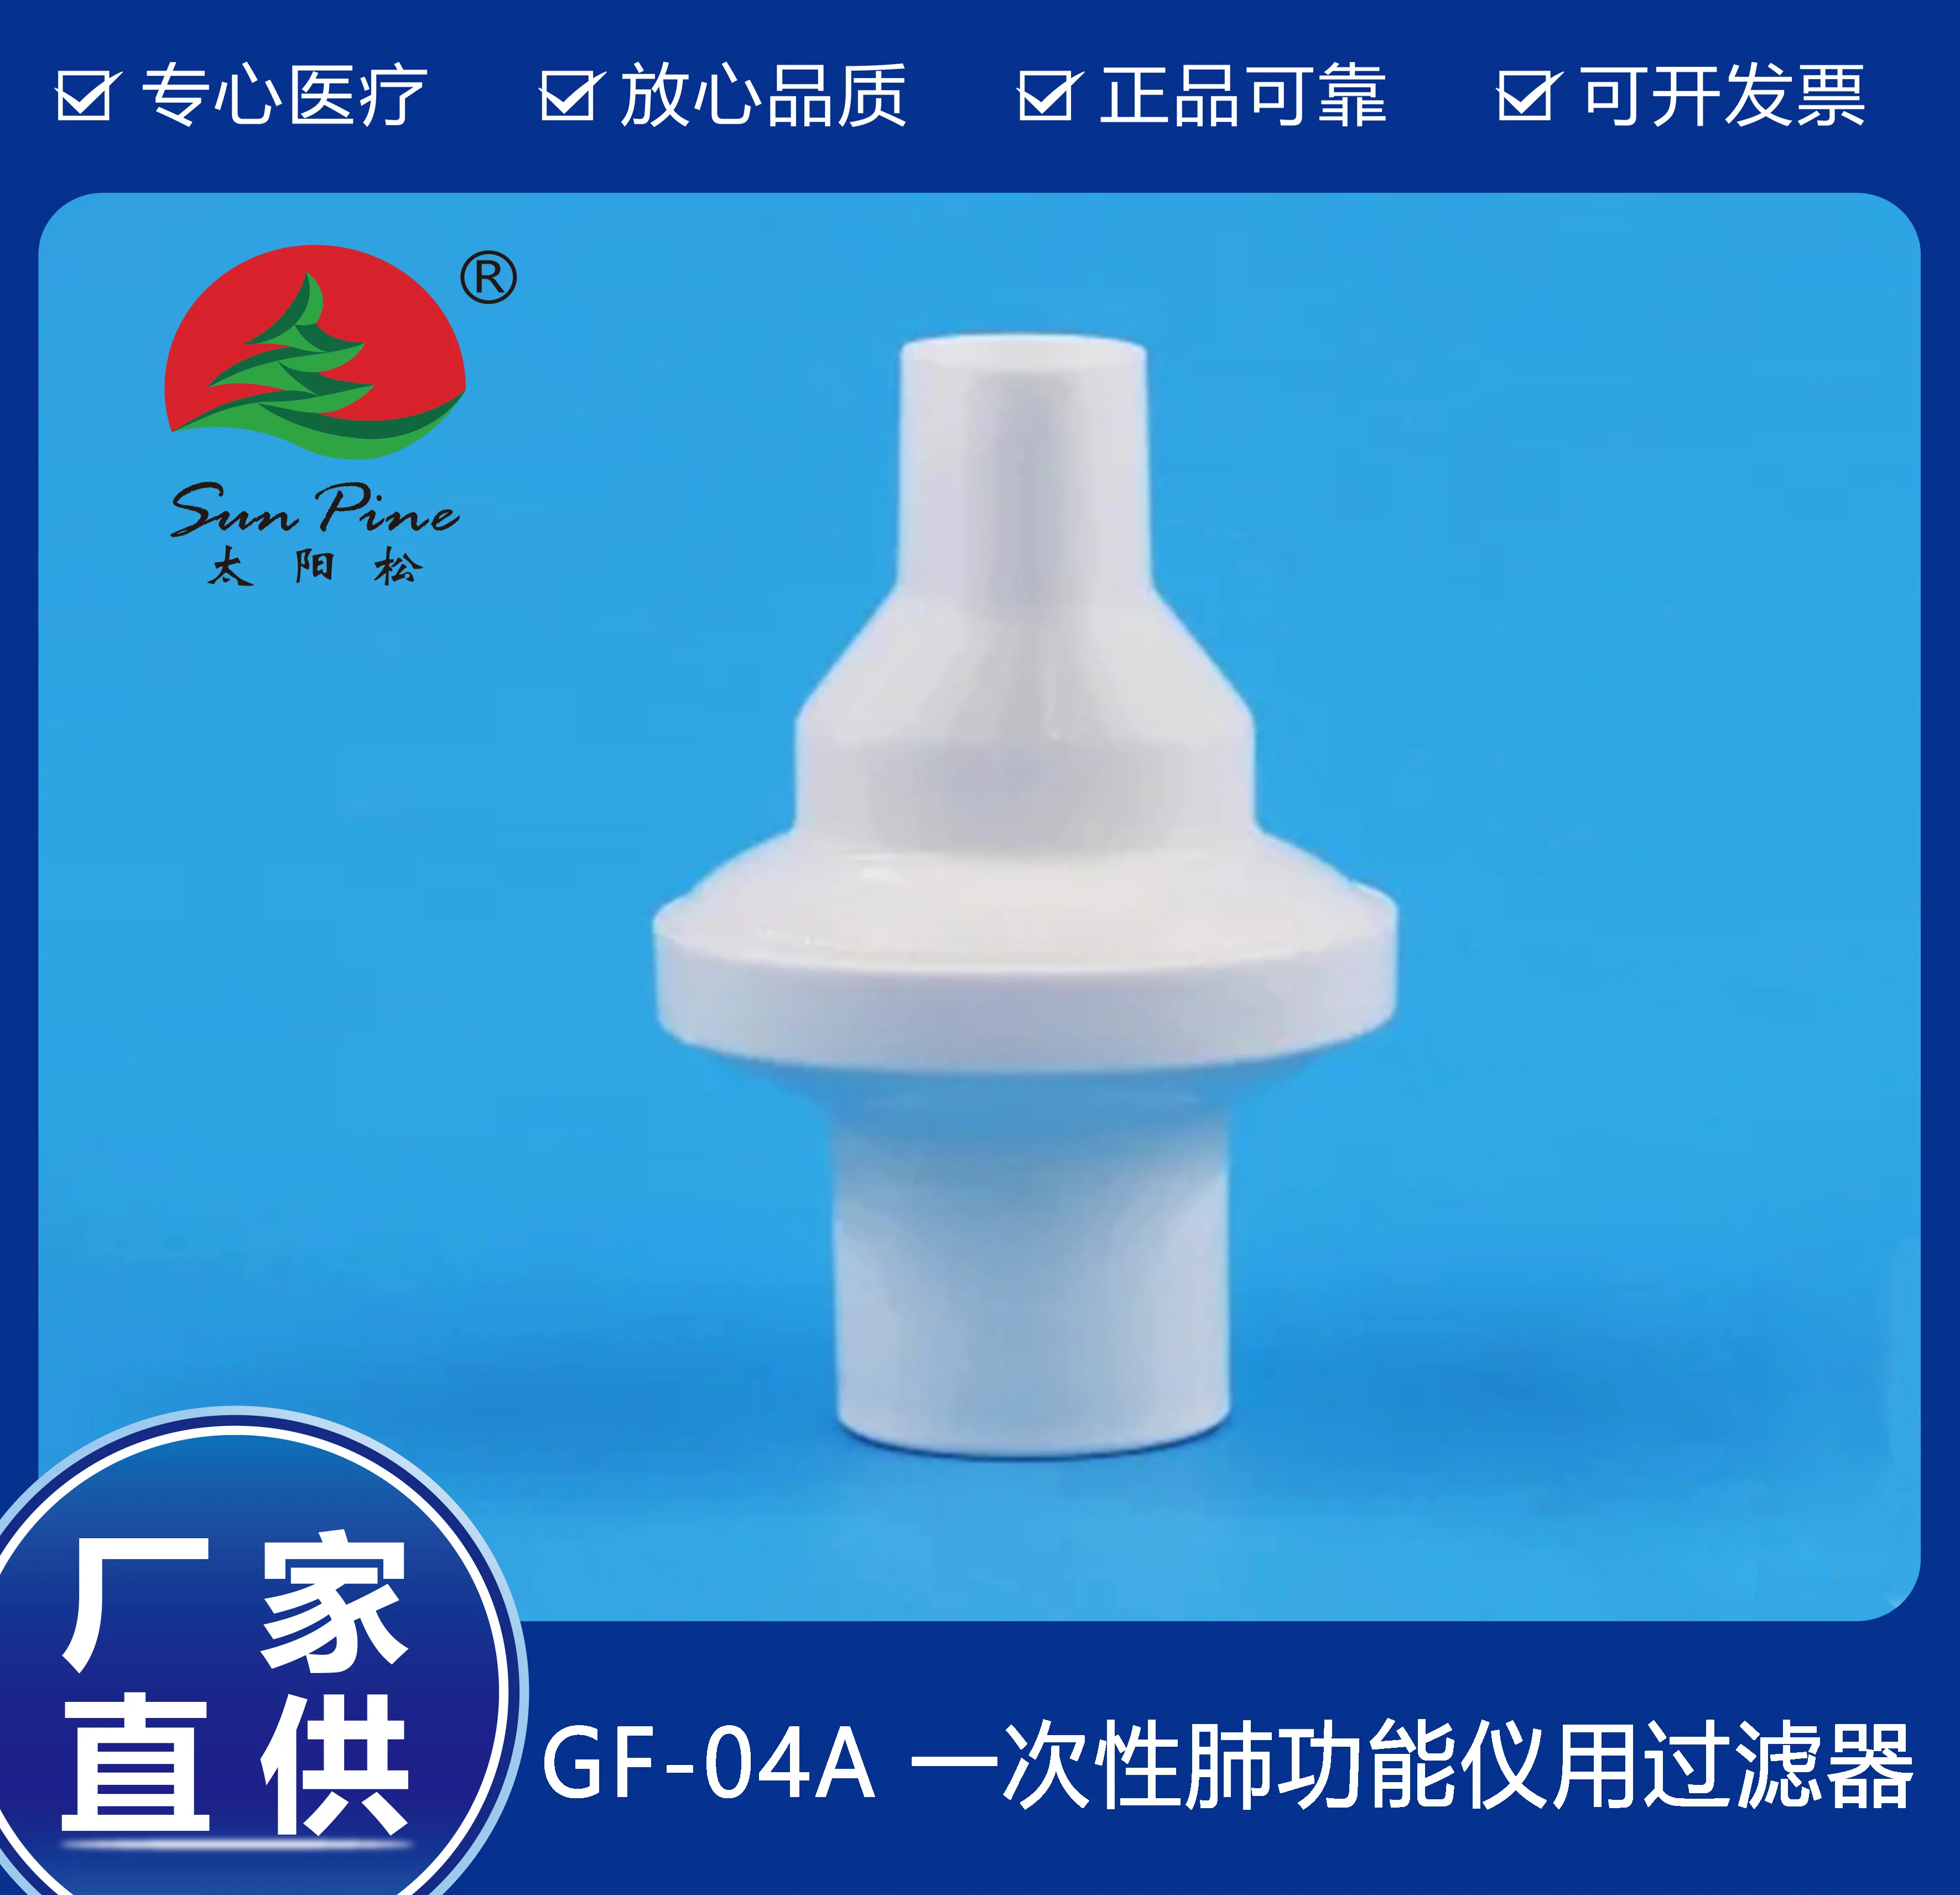

中山高榮電子科技有限公司是一家集自主研制,生產(chǎn)和銷(xiāo)售一體的高新技術(shù)醫(yī)療器械生產(chǎn)企業(yè),嚴(yán)格按照CFDA認(rèn)證,遵守國(guó)家醫(yī)療器械法規(guī)建立了完善的質(zhì)量管理體系,確保提供給客戶(hù)的醫(yī)療器械產(chǎn)品安全健康。公司擁有十萬(wàn)級(jí)、萬(wàn)級(jí)潔凈生產(chǎn)車(chē)間,環(huán)氧乙烷滅菌車(chē)間,有專(zhuān)門(mén)的物理實(shí)驗(yàn)室、理化實(shí)驗(yàn)室和微生物實(shí)驗(yàn)室以及醫(yī)電研發(fā)室、醫(yī)電生產(chǎn)車(chē)間。主要產(chǎn)品有:“太陽(yáng)松”品牌:一次性使用呼吸過(guò)濾器,一次性肺功能儀用過(guò)濾器,咬嘴;“凱華”品牌:醫(yī)用電子產(chǎn)品,肺功能檢查儀等,其中過(guò)濾器,咬嘴可匹配市場(chǎng)上各種不同品牌型號(hào)的肺功能儀使用,可以降低患者吸入或呼出顆粒性物質(zhì)的數(shù)量,防止污染儀器,大限度保障每位受測(cè)者健康安全.